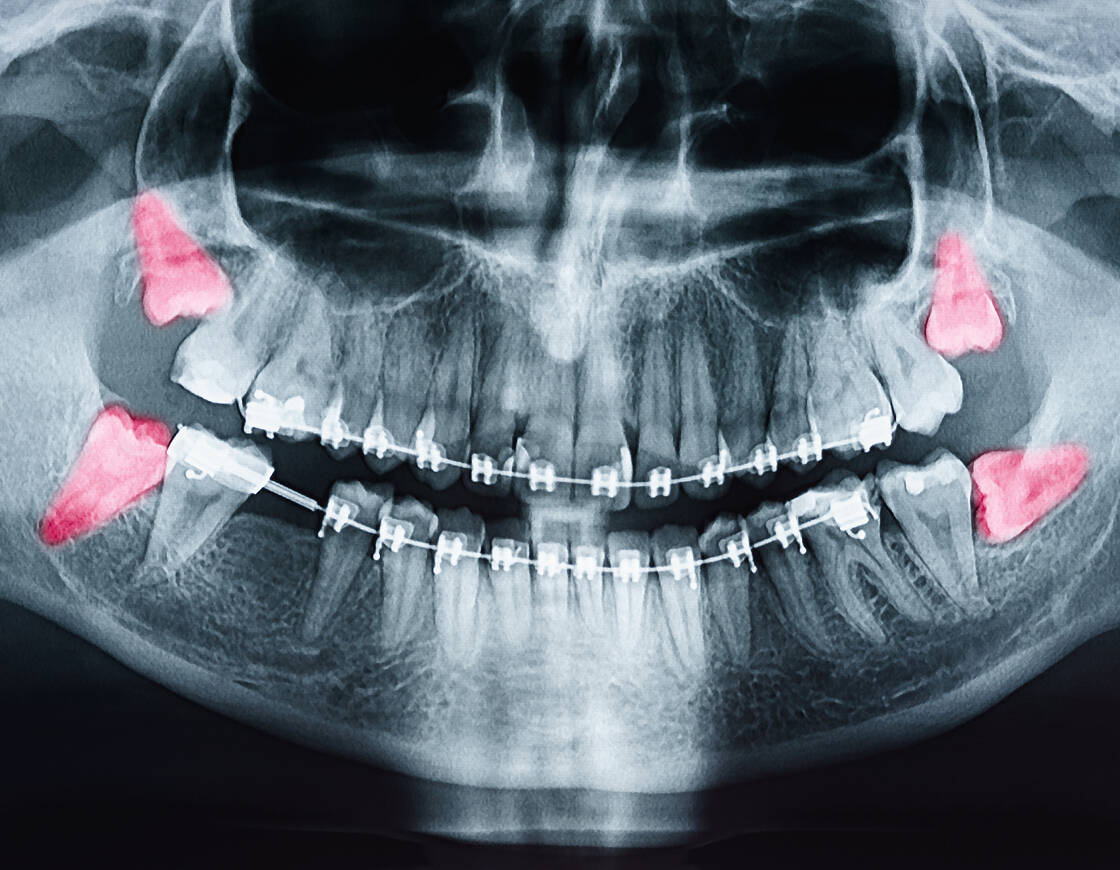

親知らずが横向きに生えていたり、歯茎や骨に埋まっている場合は、周囲の歯や神経、骨の状態を正確に把握するため、レントゲン検査やCT撮影を行い、検査後、別日の抜歯をご提案する場合がございます。

事前の詳細な診断

最先端の診断機器を用いて、事前に詳細な診断を行い、患者さま一人ひとりに最適な治療計画を立てます。

レントゲンやCT撮影を行い、親知らずの位置や状態を確認します。